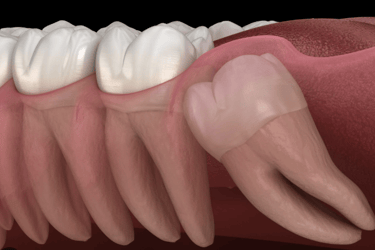

Wisdom Tooth Extraction is a surgical procedure to remove one or more third molars, also known as wisdom teeth. These teeth often grow between ages 17 and 25 and can become impacted,misaligned, or cause crowding and pain. Removing them helps prevent infection, swelling, and damage to other teeth or the jawbone.

Impacted or partially erupted

When wisdom teeth don’t fully emerge, they can trap food and bacteria, causing pain, swelling, and infections in the gums or jaw.

Cysts or jawbone damage

In some cases, impacted teeth can form cysts that damage nearby teeth, nerves, or bone structure,

requiring surgical removal.